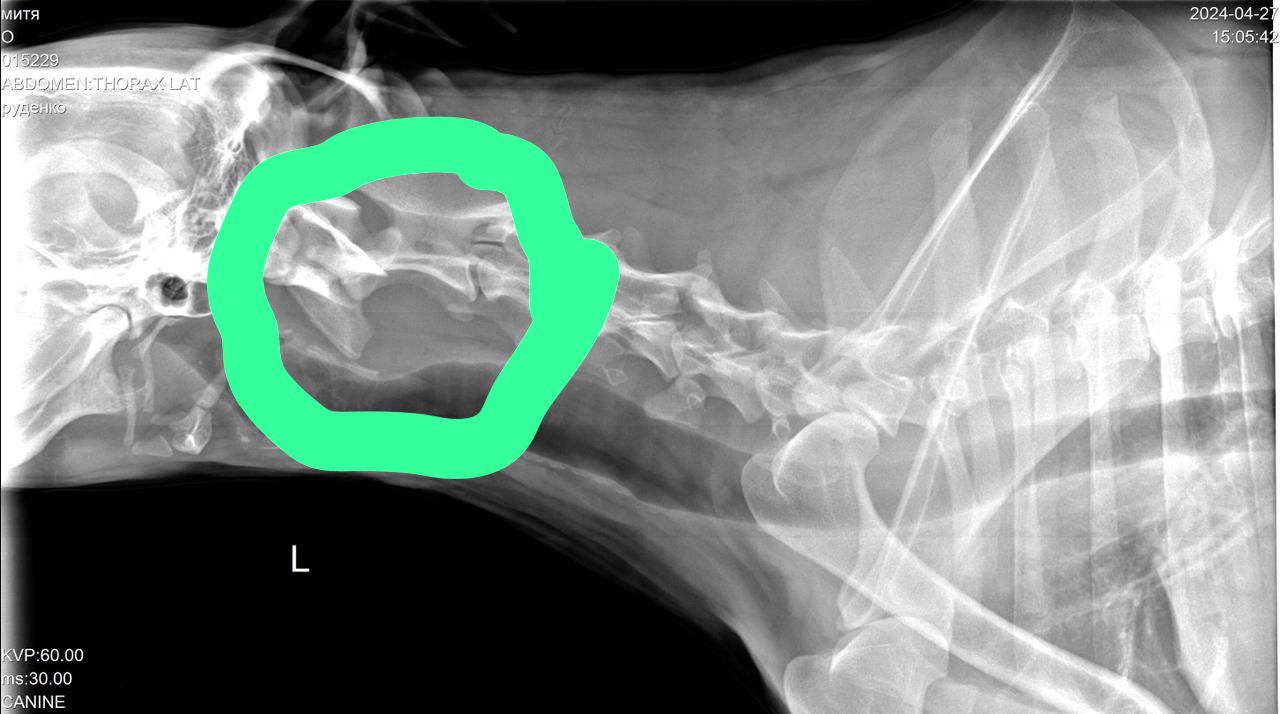

Сегодня Катюша возила Митю на рентген.

Вложения

IMG-20240427-WA0028.jpg

IMG-20240427-WA0029.jpg

IMG-20240427-WA0030.jpg

IMG-20240427-WA0031.jpg

IMG-20240427-WA0032.jpg